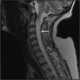

Necrotizing vasculitis

Vasculitis is a group of disorders that destroy blood vessels by inflammation. Both arteries and veins are affected. [Source: Wikipedia ]